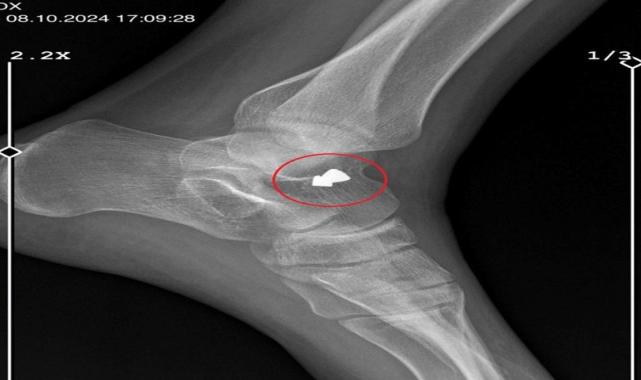

Ayak kemiğim çatlamış, alçıya bu yüzden aldılar. Eve geldiğimde e-Nabız uygulamasından röntgenime baktığımda, saçmanın ayağımın içinde kaldığını gördüm; ama beni bir daha hastaneye götürmedi" diye konuştu.

Yalova'ya döndükten sonra, 19 Ekim'de sol kemiğine isabet eden saçmanın ameliyat ile çıkarıldığını söyleyen Ayşe Ç., "Evden kaçabilmem için bir imkan yoktu. A.K., en son gün, evden gitmeden önce beni darbetti. Saçlarımdan tutarak, yerde ayakkabılarıyla tekmeledi. Sonra evden gitti.

Arkadaşıma konuyu anlattığımda, o beni hastaneye götürdü. Daha yeni ameliyat oldum. Saçmayı çıkarttılar, şu an dikişli ayağım. Bu insan, bende kalıcı bir hasar bıraktı" diye konuştu.